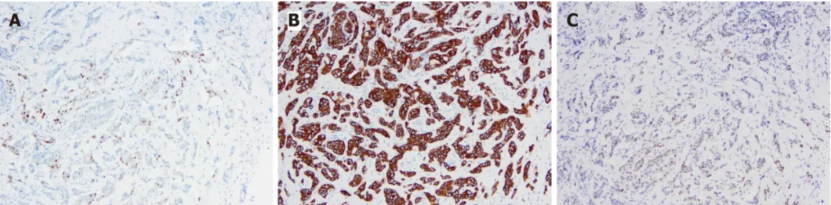

为进一步明确阴茎肿块性质,患者接受了冠状沟处三个肿块的局部手术切除。切除肿块的组织病理学检查显示为低分化腺癌,与原发结肠肿瘤一致(图3)。免疫组化检查显示CDX2、CK20和SATB2阳性表达,表明阴茎肿块起源于结肠(图4)。

图4. 阴茎肿块的免疫组化染色结果表明其起源于结肠

图4. 阴茎肿块的免疫组化染色结果表明其起源于结肠最终诊断